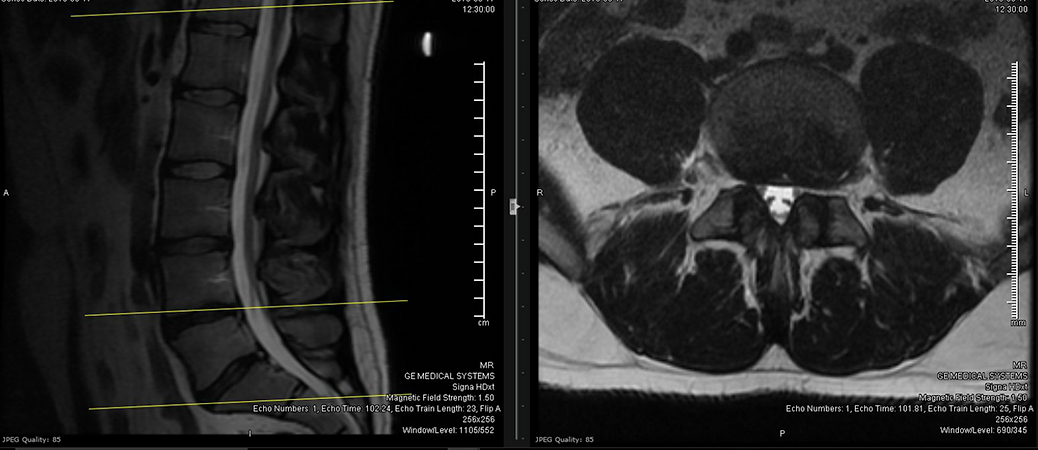

- Obtain a new MRI of the lumbar spine